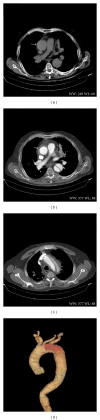

We reported a case of 68-year-old man, with a previous history of hypertension. Patient was admitted to our institution for evaluation of a severe, constant, tearing anterior chest pain radiated to the neck with suspicion of acute aortic dissection. A multidetector computed tomography scan of thorax and abdomen demonstrated a dissection starting from the middle part of aortic arch and extending downward to the descending aorta till the middle part of the thoracic aorta. The dissection was classified as Stanford A, De Bakey I. Surgical treatment of patient was started with bypass graft from the right common carotid artery to the left common carotid with subsequent revascularization of left subclavian artery. Lower parts of above-mentioned arteries were ligated. At the second stage an emergent prosthetic stent-graft was placed distally from the truncus brachiocephalicus up to the proximal part of the descending aorta. We reported a case report to present diagnostic and possible interventional treatment for patient with acute aortic type A dissection.